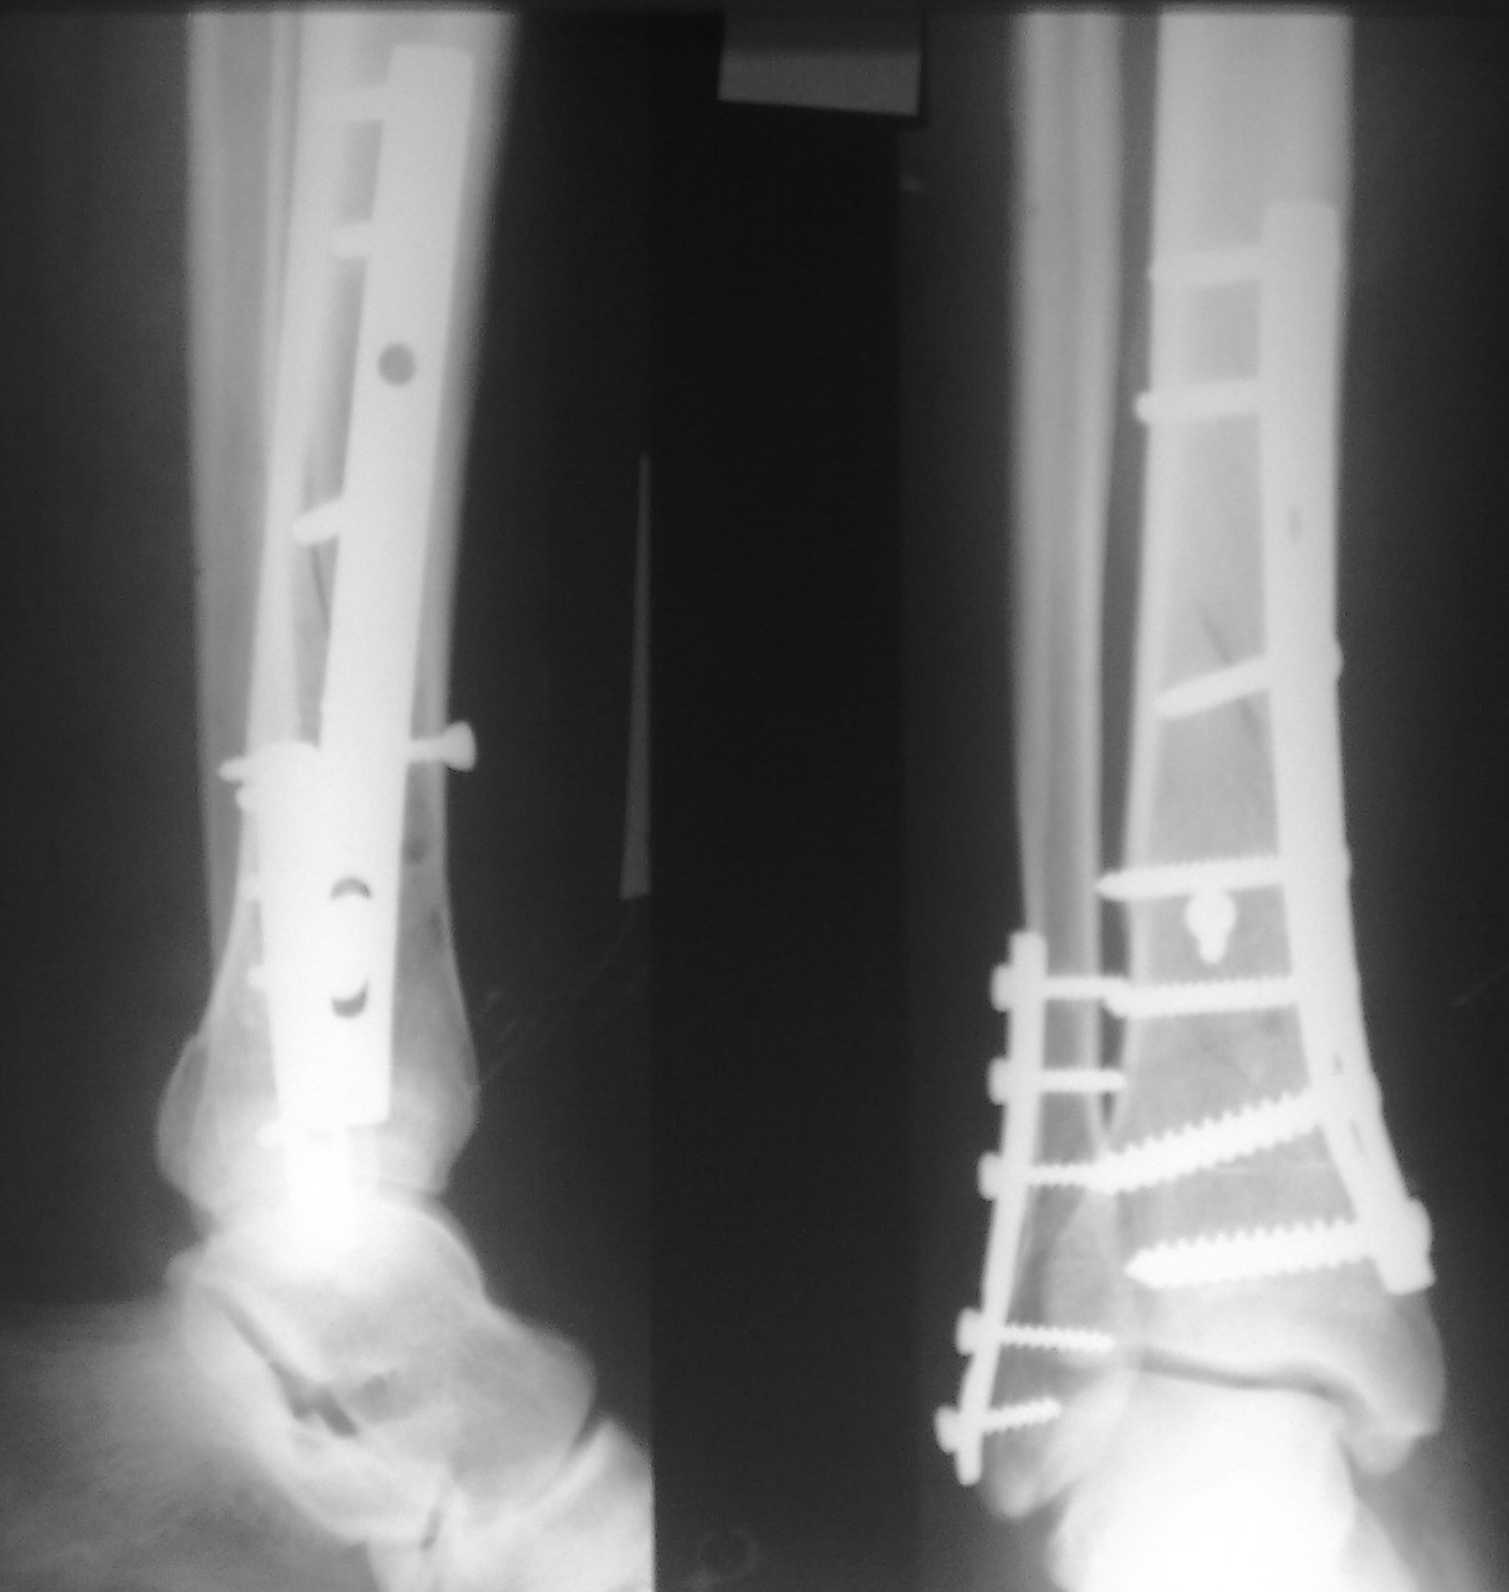

Спасибо за советы. Выполнен МОС обоих костей голени